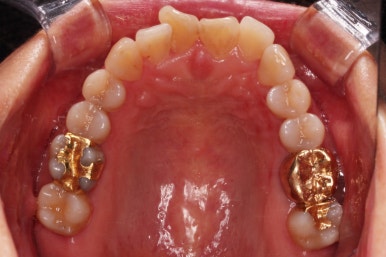

동래임플란트교정 초진 시 입안의 모습입니다.

치열이 전반적으로 삐뚤어져 있는 양상이고요.

아랫니가 윗니보다 더 많이 삐뚤어 있는데요.